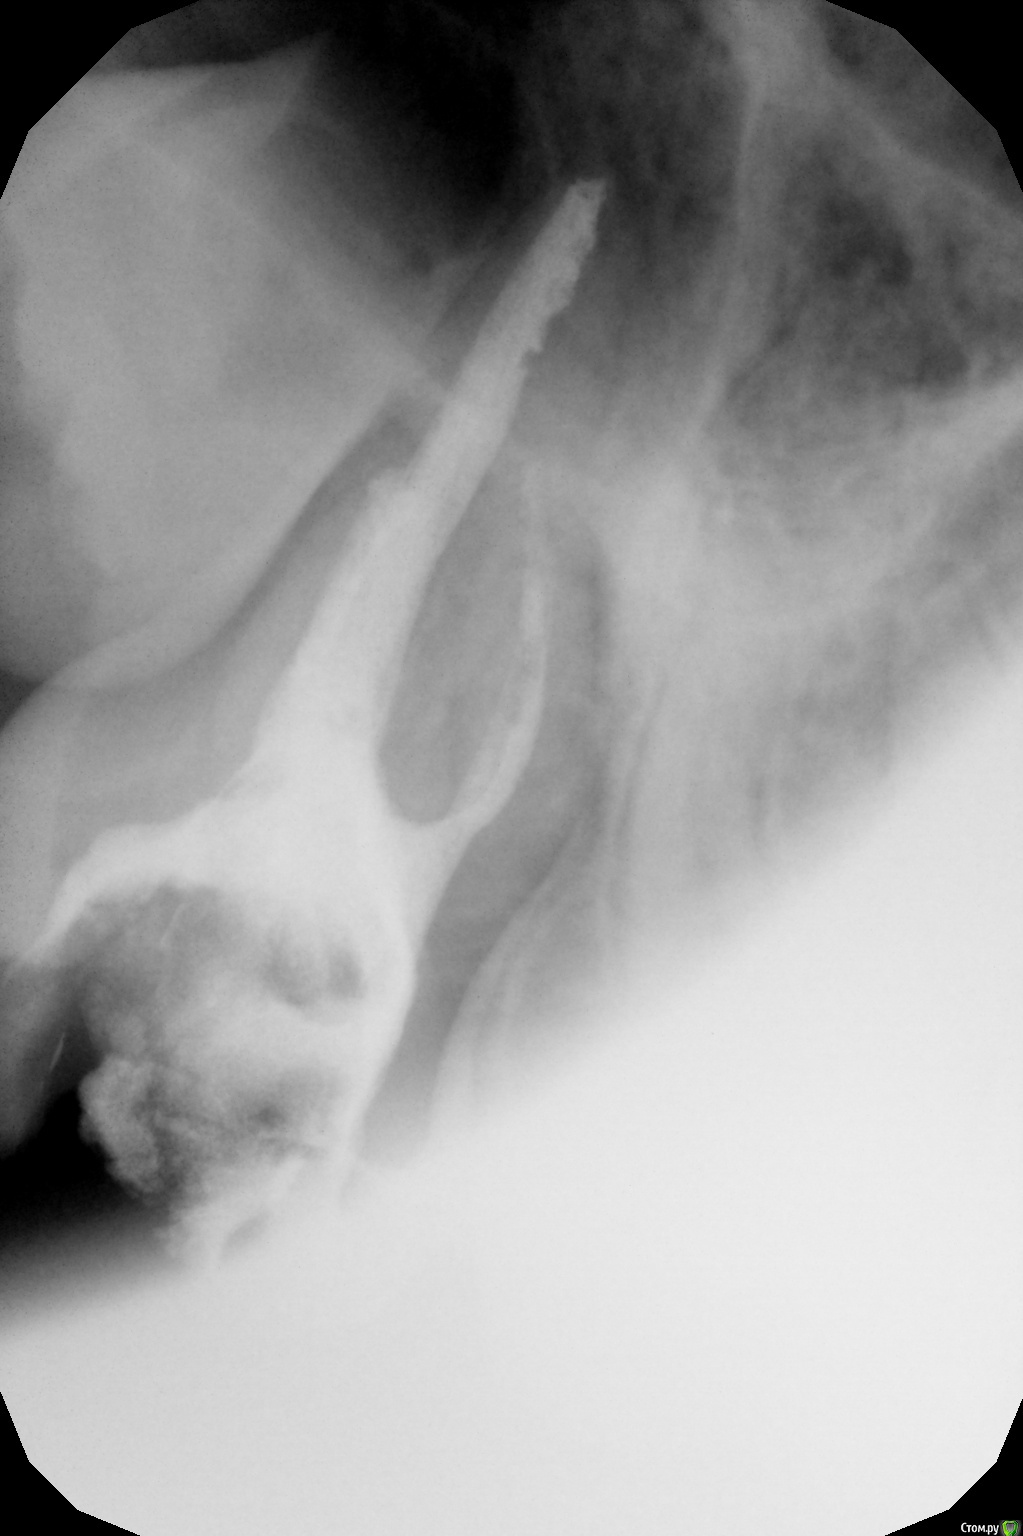

crown Опубликовано 7 мая, 2016 Автор Поделиться Опубликовано 7 мая, 2016 (изменено) Девочка, 14 лет. Диффузный пульпит 17. В щечных получилось создать упор на 40 файле. В небном 70 проваливается за апекс. Запломбировал метапексом, правда без коффера, были сложности с наложением и доступом. Закроется верхушка или нет? Изменено 7 мая, 2016 пользователем crown Ссылка на комментарий

Джима Опубликовано 7 мая, 2016 Поделиться Опубликовано 7 мая, 2016 Закроется, наверно. Только, возможно, придётся добавлять метапекс через время.чего мта апекс не сделали? прямой канал, широкий..чего не удалили вообще ? не рассматривали такой вариант? Ссылка на комментарий

crown Опубликовано 8 мая, 2016 Автор Поделиться Опубликовано 8 мая, 2016 Так как корни не сформированы решил в эту тему закинуть. От удаления отказались, там еще одна такая нижняя семерка. МТА даже не пытался, доступ не удобный, а сносить пол коронки не хочется, да и без оптики я думаю не получится, все размажу по стенкам, другое дело центральный зуб, там попроще . Ссылка на комментарий